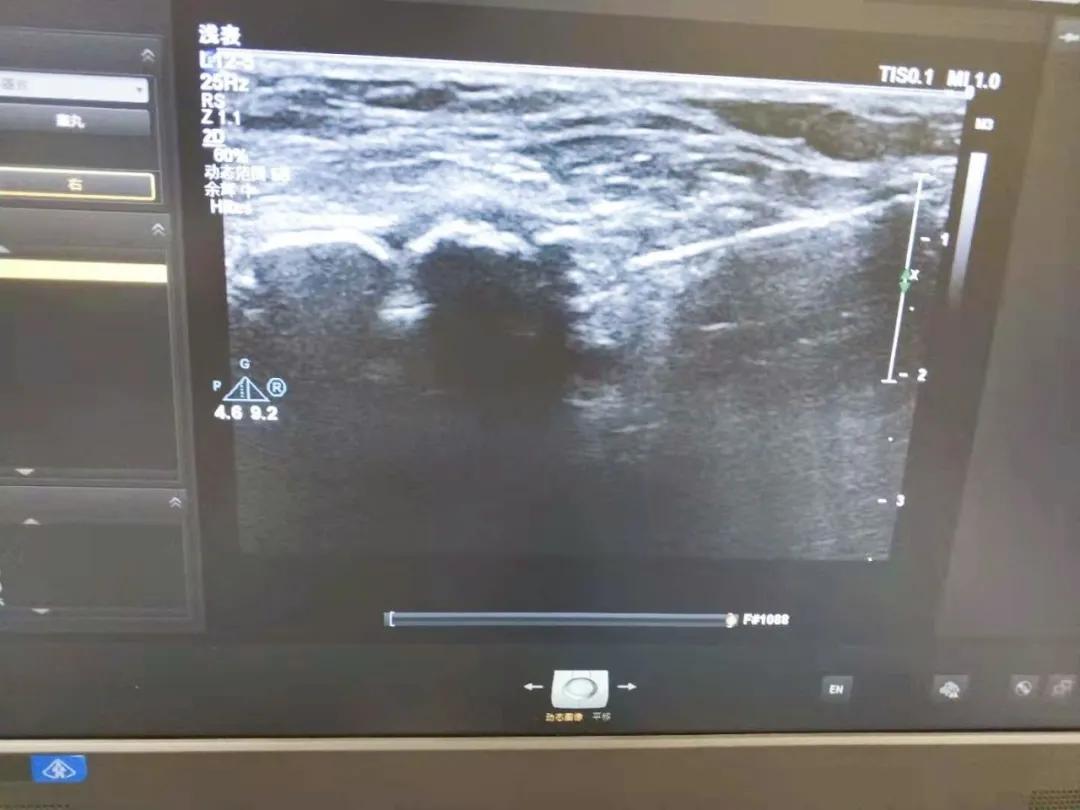

在仔细询问了超声科主任、副主任医师夏克良后,患者决定于5月18日进行皮下的微创手术,这也是首次我院进行腘窝囊肿的治疗。为减轻患者对于手术的紧张情绪,夏克良主任通过超声检查以及多年的经验,为患者讲解了术前的准备事项,术中操作的流程以及术后康复等一系列有关知识。

在患者以及家属同意后,在夏克良主任以及刘庆坤医师的配合下,顺利抽出囊肿液体,并给患者反复冲洗抽出残余囊肿液体,整个手术过程时间大约一个小时,术中患者无明显痛感,术后夏克良主任也告知患者术后注意事项,再给患者仔细包扎创口后,患者及其家属给予了高度评价。

夏克良主任说,随着超声技术的日益成熟,很多疾病都可在病变的前期及时发现并作出正确的医学判断,通过超声引导,运用穿刺针和超声影像的实时引导,边操作边注意手术的完成度,通过经皮穿刺,抽吸,活检,引流,用药等一系列微创操作,使患者受到最小的痛苦,获得最好的疗效,像肝囊肿,肾囊肿等一系列囊肿,都可在超声介入技术的帮助下进行手术,具有创口小,费用低,术后恢复好,痛感小等一系列优势。